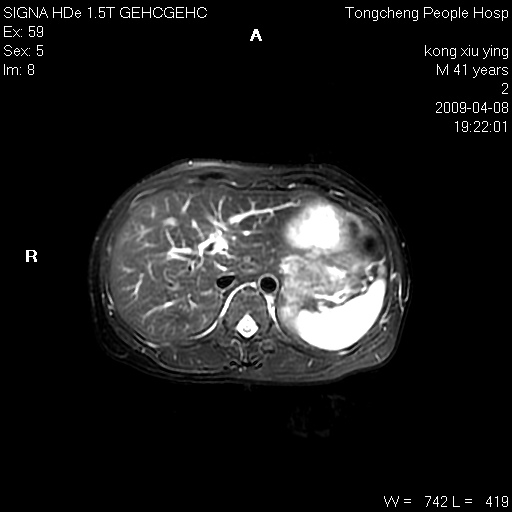

标题: CL1008:【经典】胆囊石榴籽样结石。

女,41岁。健康体检——彩超提示:胆囊显示不清。平素健康,无不适感。

腹部mr扫描及mrcp,图像如下: